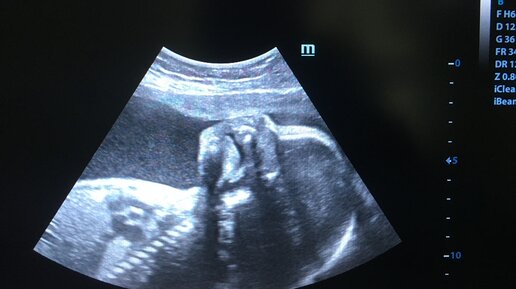

Определение ПОЛА ребенка по крови матери, с 9 недели беременности с ТОЧНОСТЬЮ до 99%. Проверено лично. Безопасно.

Я узнала пол 3-го ребенка в 9 недель беременности. Безболезненно и быстро (за несколько дней). Всего, взяли кровь (венозную) и несколько тыс рублей. Да, это процедура не приятная, только, в денежном плане. У меня старшие дети «мальчик и …еще один мальчик», конечно любопытство взяло ВЕРХ над «Жабой» и пониманием, того, что любить мы и так, будим третьего карапуза. Главное здоровье!

Ровно год назад, в сентябре-октябре 2022 года мы ждали ребёнка. Перед тем как становиться на учёт в женскую консультацию, было принято решение сначала сдать неинвазивный пренатальный тест на генетические отклонения, и уже с результатами этого теста прийти в женскую, чтобы нервы не трепали дополнительными исследованиями. Я очень много читала информации о НИПТ в прошлом году и собиралась его сдавать на 10-недельном сроке, как и рекомендуется. Правда, в Нягани тогда этот тест ещё не делали, только...